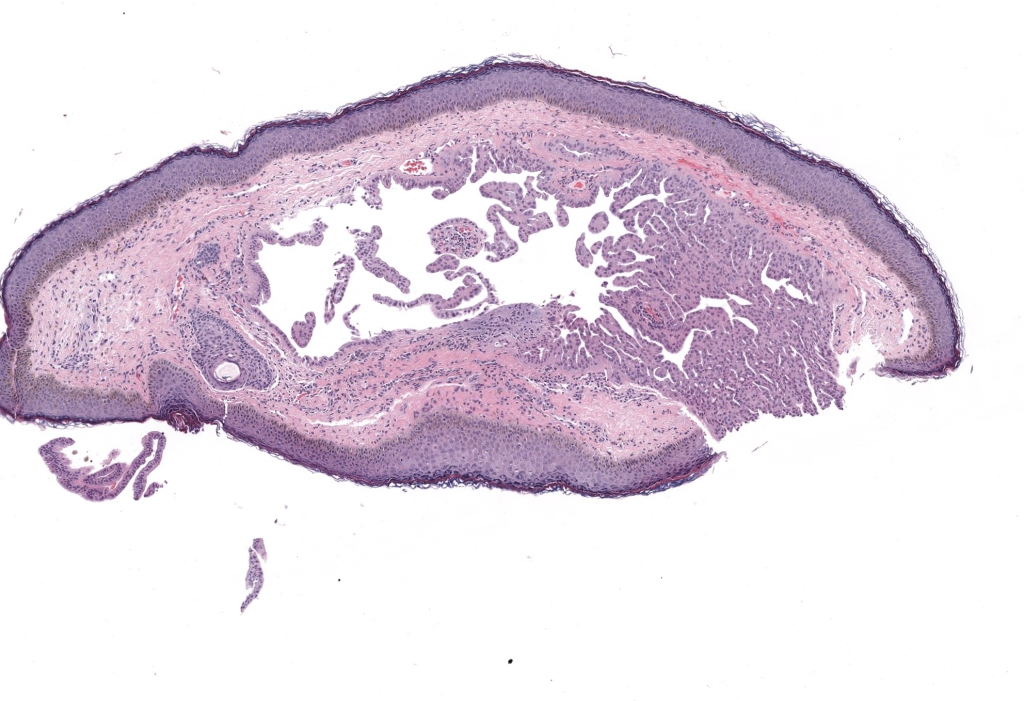

Nombres alternativos: quiste sudoríparo; quiste de glándulas de Moll (apocrino); “tipo Robinson” (múltiple eccrino).

Primera descripción: múltiples hidrocistomas eccrinos descritos por Robinson (1893); el apocrino (cystadenoma/hidrocistoma) delineado por Smith & Chernosky (1974).

Epidemiología: adultos de mediana edad y mayores; predominio femenino en formas múltiples eccrinas; localización facial periocular; rara afectación orbitária/conjuntival/carúncula. Exacerban con calor/humedad (estacionalidad).